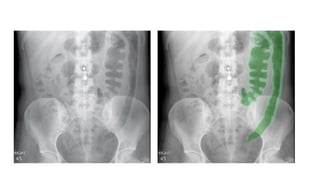

SPINE PATHOLOGY

1. Vertebral body height

2. Alignment

3. Pedicles (metastases)